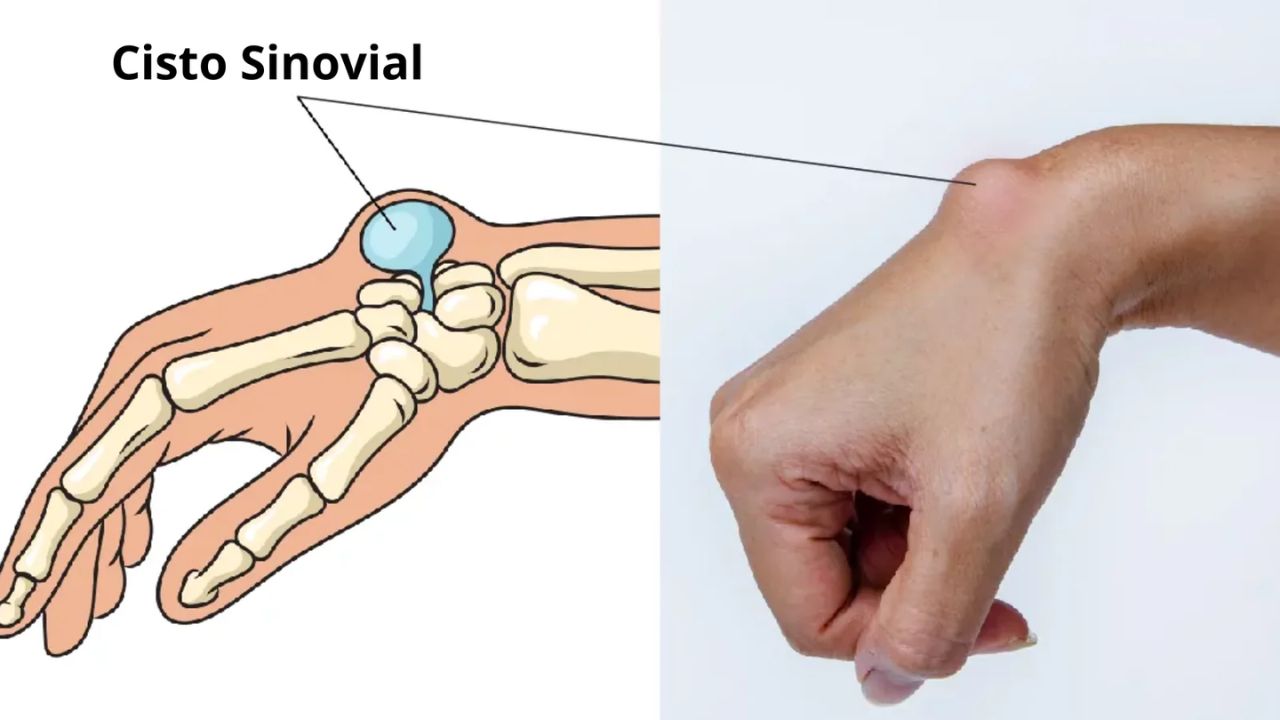

Cisto Sinovial Agendar consulta O cisto sinovial é um nódulo comum que surge próximo a articulações ou tendões, sendo extremamente frequente na região do punho.